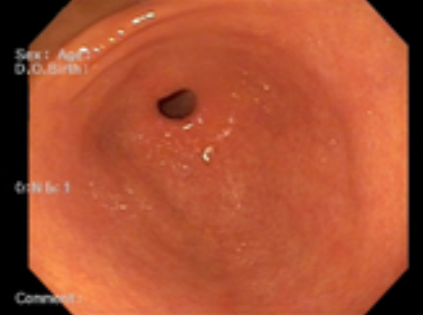

위내시경 검사는 위나 십이지장, 식도를 내시경 카메라로 살펴보는 검사로 평소 소화가 잘 되지 않거나 더부륵함, 메스꺼움, 복통, 속 쓰림, 구토 증상 등이 있다면 위염, 역류성식도염, 위용종, 위궤양, 위출혈, 십이지장질환, 위암, 식도암 등이 있을 수 있으므로 꼭 해보는 것을 권장드립니다.

위내시경 검사의 방법은 수면과 비수면으로 진행되는데 비수면 위내시경 검사의 소요 시간이 5분~10분 정도밖에 걸리지 않아 빠르고 간편합니다. 비수면 위내시경 검사의 경우 직접 본인의 위 상태를 직접 눈으로 볼 수 있어 조금 더 위 건강에 신경 쓸 수 있다는 장점이 있습니다.

위내시경 검사 중 조직검사를 통해 헬리코박터 감염 여부도 확인할 수 있습니다. 헬리코박터 파일로리 균 검사의 경우 1~2일이 지나면 결과를 알 수 있고, 조직 검사의 경우 7일에서 10일 정도 후 감염여부를 알 수 있습니다. 한 의료기관에서 위내시경 검사를 받았다면 2년 뒤에도 같은 병원에서 정기적으로 진행하는 것이 환자한테 좋습니다.